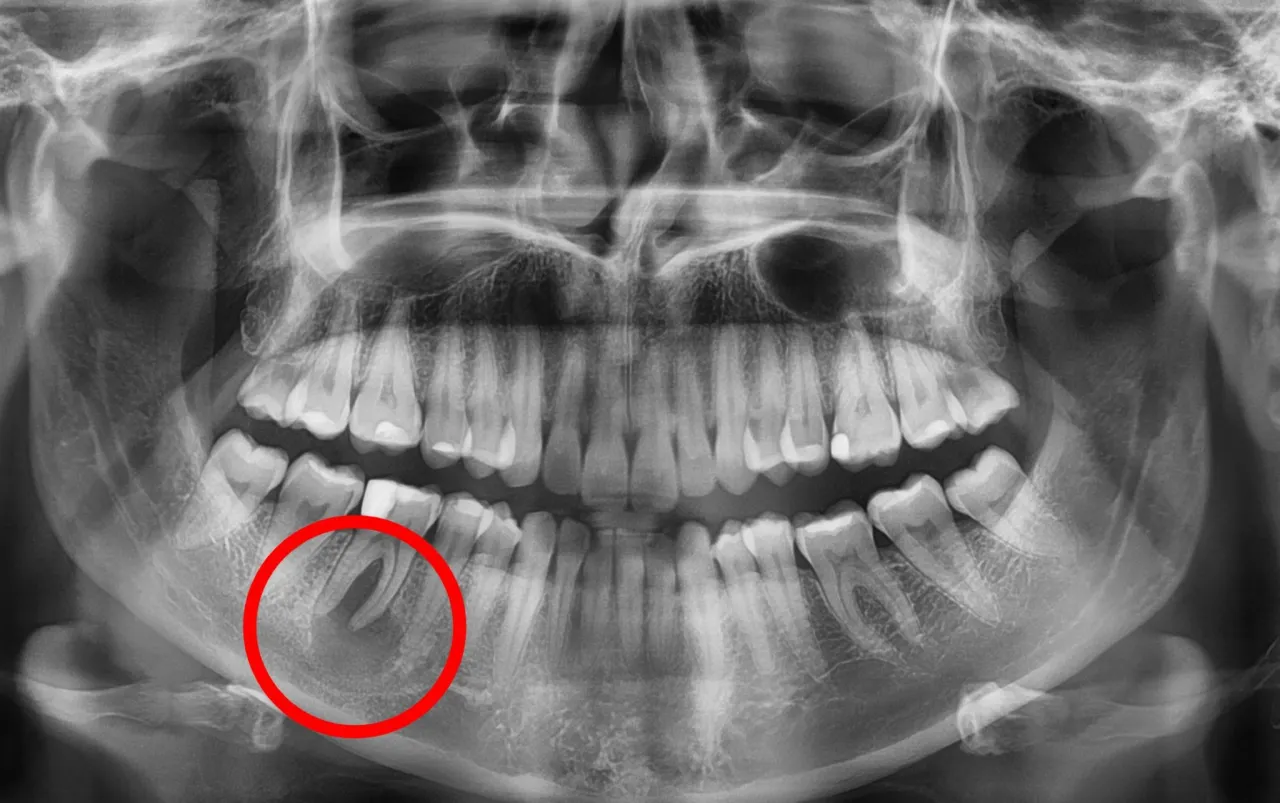

Rola zdjęcia RTG: dlaczego obraz jest kluczowy dla postawienia diagnozy?

Diagnostyka torbieli opiera się na kilku filarach, ale absolutną podstawą jest diagnostyka obrazowa, a zwłaszcza zdjęcie RTG. Na zdjęciu rentgenowskim, czy to pantomograficznym (obejmującym całe uzębienie), czy punktowym (skupiającym się na konkretnym obszarze), torbiel jest widoczna jako wyraźne, ciemniejsze przejaśnienie w kości. To właśnie ten obraz pozwala mi ocenić jej rozmiar, lokalizację i stosunek do sąsiednich struktur. W bardziej skomplikowanych przypadkach, gdy potrzebuję trójwymiarowego obrazu, na przykład w celu oceny bliskości torbieli do nerwów czy zatok, wykorzystuję tomografię komputerową (CBCT). To narzędzie daje mi pełny obraz sytuacji i pozwala na precyzyjne zaplanowanie leczenia.